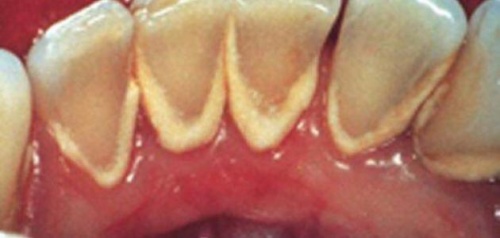

كيف أتخلص من طبقة الترسبات على أسناني ؟

الجير هو طبقة من الترسبات يتعرض لها جميع أنواع الأسنان، مما يؤدي إلى خشونة سطح الأسنان و تغير لونها، كما يمكن أن يؤدي تجمع الجير على الأسنان إلى تسوسها أو الإصابة بأمراض اللثة، إن العناية اليومية بالأسنان تمنع تشكل هذه الطبقة، و بالتالي فإن هذه الخطوة تعتبر الأولى نحو تنظيف الاسنان من الجير.

تنظيف الأسنان من الجير

لكن على كل حال يمكن إزالة هذه الطبقة و منع تشكلها، و يمكن تنظيف الأسنان بأكثر من طريقة و في ما يلي أبرز هذه الطرق.